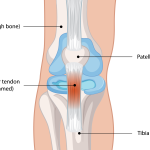

Understanding ACL Injuries: Causes, Symptoms & Recovery Patellar Tendinopathy: Understanding Knee Pain Below the Kneecap

Patellar Tendinopathy: Understanding Knee Pain Below the Kneecap Cervicogenic Headache: When Your Neck Is the Real Cause of Your Headache